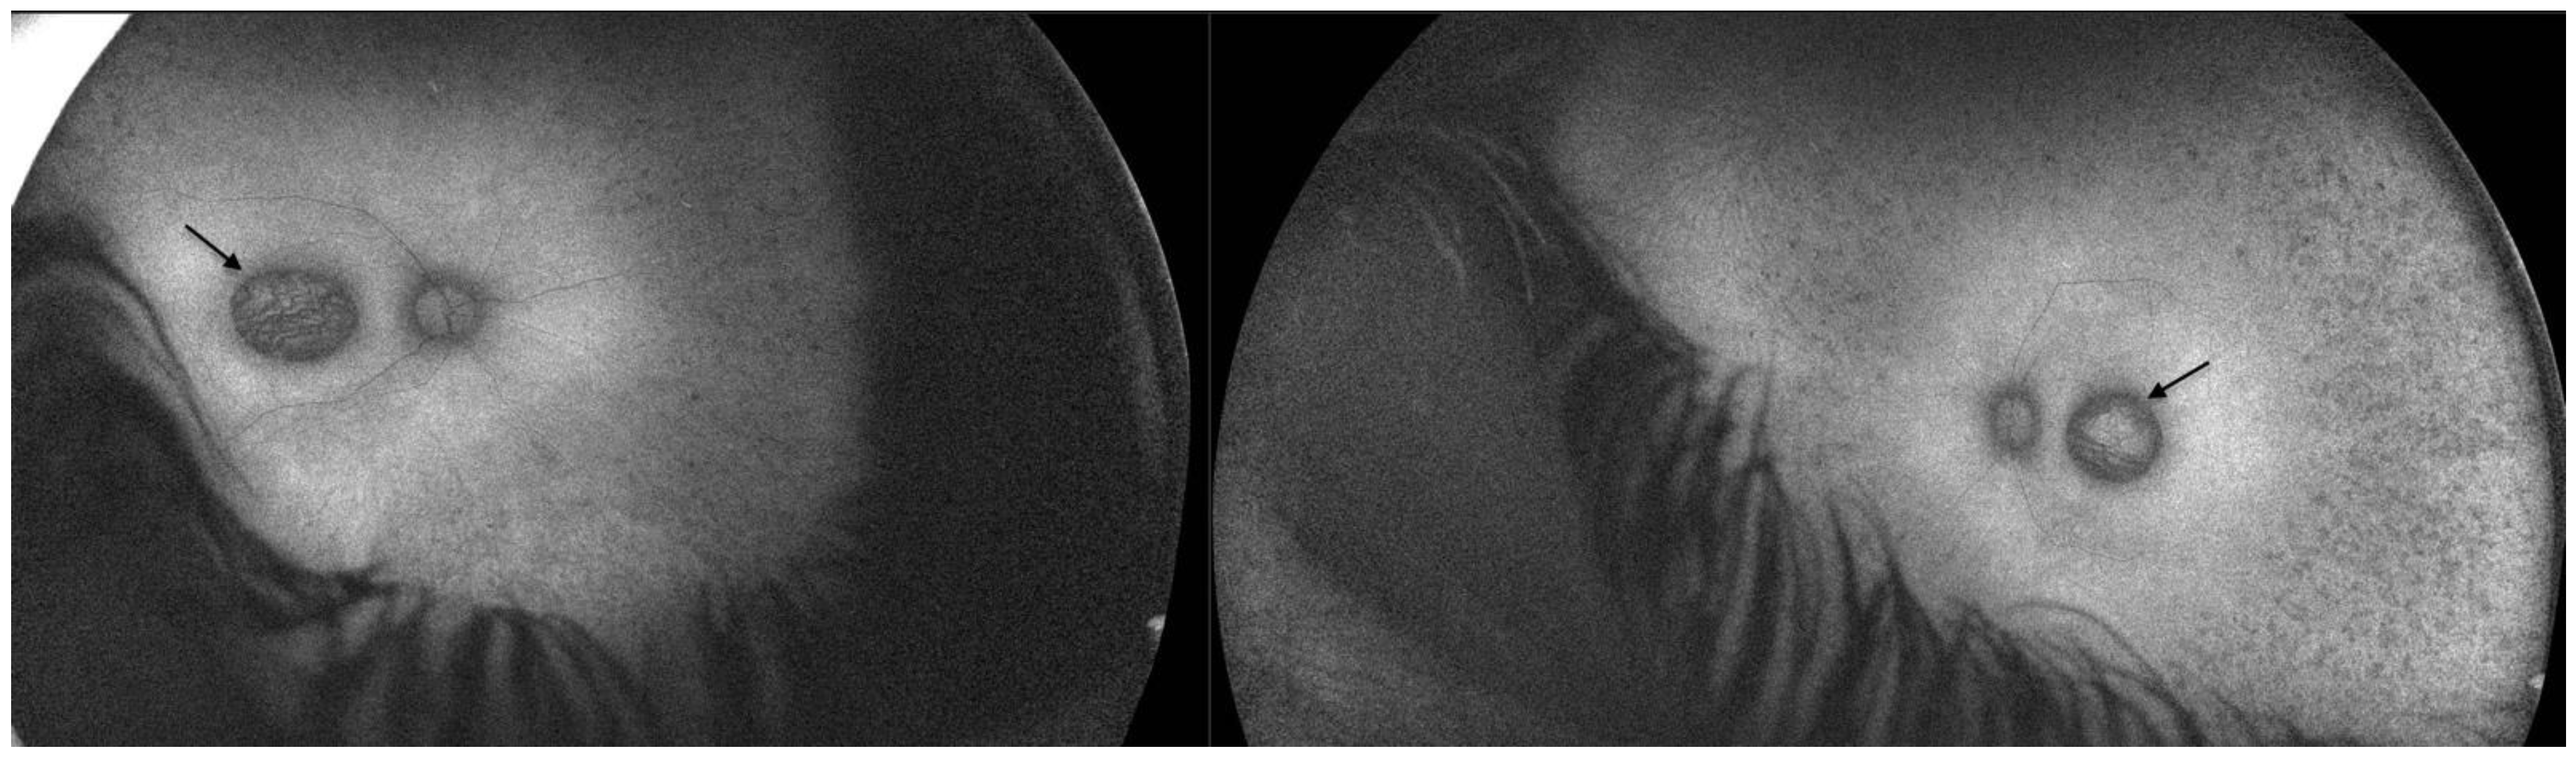

2.1. Patient 1

2.2. Patient 2